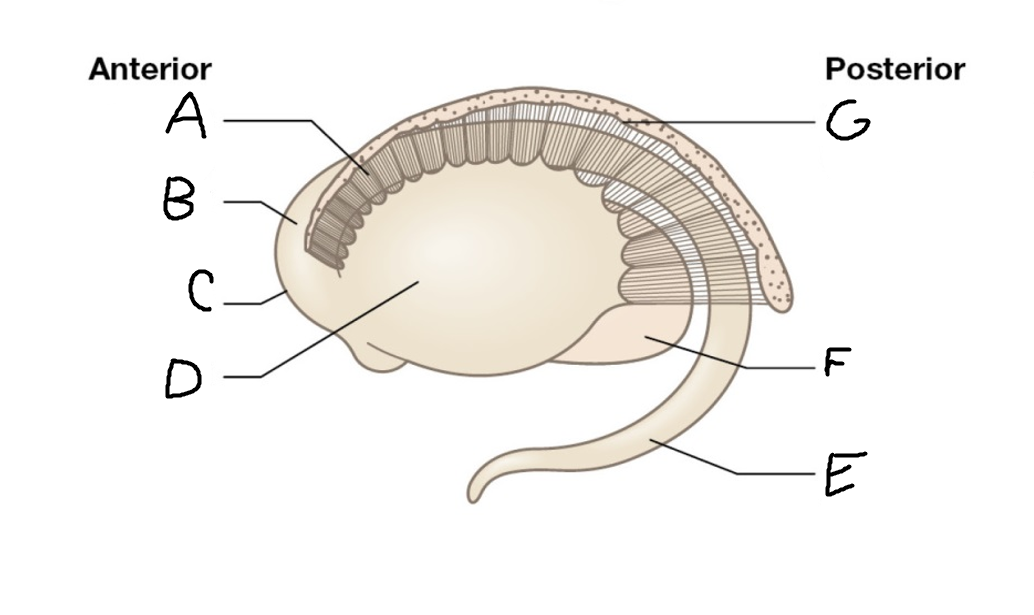

A

internal capsule (anterior limb)

B

caudate nucleus body

C

caudate nucleus head

D

putamen

E

caudate nucleus tail

F

thalamus

G

internal capsule (posterior limb)